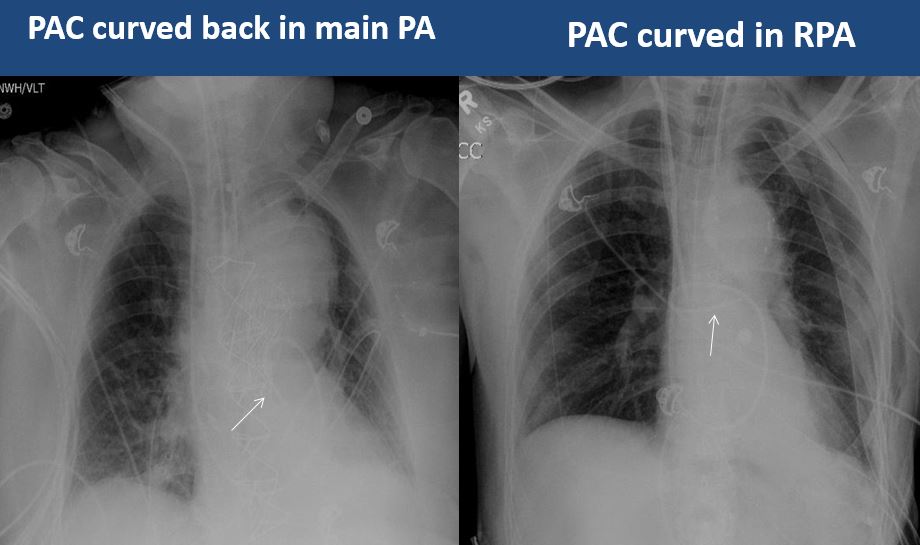

There is a PAC in place that is not in a main pulmonary artery or is otherwise abnormal. [Yes/No]